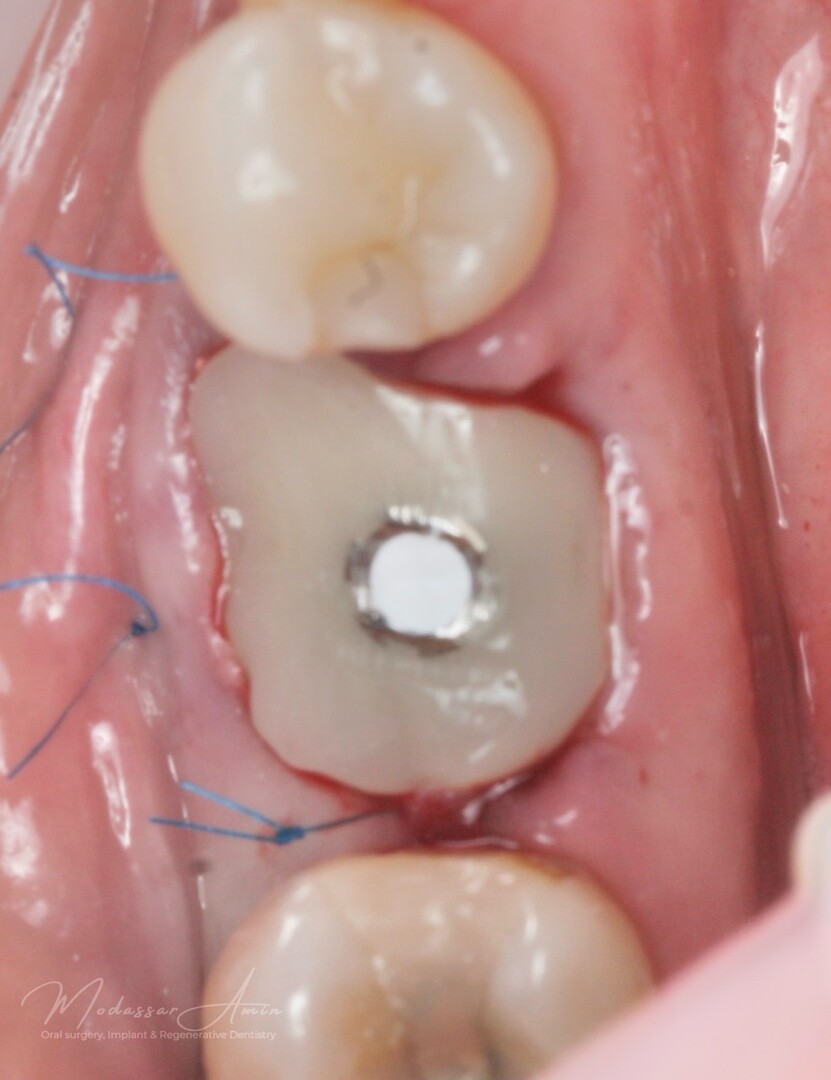

PATIENTFALL

"Pasienten presenterte med tann 46 som ikke kunne bevares grunnet en dyptgående infraksjon inn i furkasjonen. Forholdene lå til rette for en immediate implantatbehandling. Ved hjelp av Versah osseodensifikasjonsbor ble det interradikulære beinet ekspandert på en skånsom og forutsigbar måte, noe som ga høy primærstabilitet (>40 Ncm) til tross for en lokal bendefekt apikalt mesialt etter kronisk apikal periodontitt. Den gode stabiliteten muliggjorde bruk av SSA (Sealing Socket Abutment) for forsegling. På grunn av tynn bløtvevsfenotype bukkalt ble behandlingen supplert med bindevevstransplantat (CTG)"

SSA (Sealing Socket Abutment) + CTG (bindvävstransplantat)